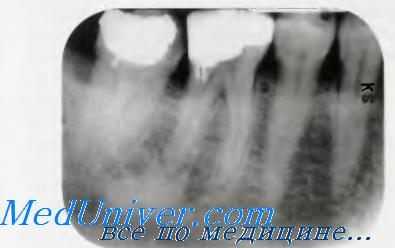

(Слева) На периапикальной рентгенограмме определяется идиопатический остеосклероз (ИО) В у вершины корня клыка нижней челюсти справа. Обратите внимание на просветление, наличие которого позволяет спутать имеющиеся изменения со склерозирующим остеитом. Визуализация интактного апикального пространства НДС в отсутствие патологии коронки помогает в дифференциальной диагностике.

(Справа) На периапикальной рентгенограмме нижней челюсти справа определяется склероз лунки после удаления зуба. Сравните с фрагментом корня второго временного моляра, окруженного тонким просветлением по периферии, представляющим собой пространство НДС.

о Хорошо отграниченное затемнение:

- Наиболее часто однородной высокой плотности с возможными просветлениями в структуре

о Может вплотную прилежать к вершинам корней зубов:

- Дифференцируйте со склерозирующим (конденсирующим) остеитом: отсутствует воспалительный процесс, не изменено пространство периодонтальной связки (ПДС)